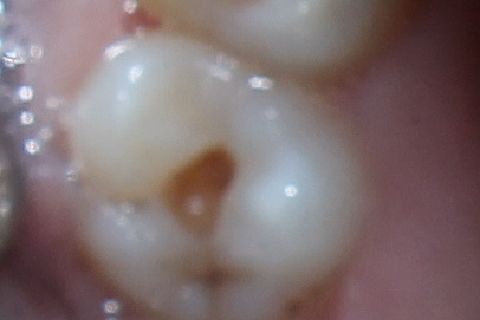

Aspecto inicial do dente apresentando lesão cariosa no sulco principal